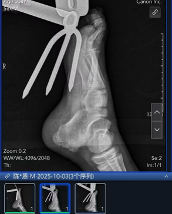

到院后,急诊科医生先对小王的伤口进行了初步清理和检查,随后送往手术室进行异物拔除手术,铁铲虽然扎穿了足底,万幸没有伤到骨头,但术中显示损伤最深达肌肉层。经过一个多小时的手术,扎在足底的铁铲成功取出,术后小王顺利返回病房,目前正在恢复中。